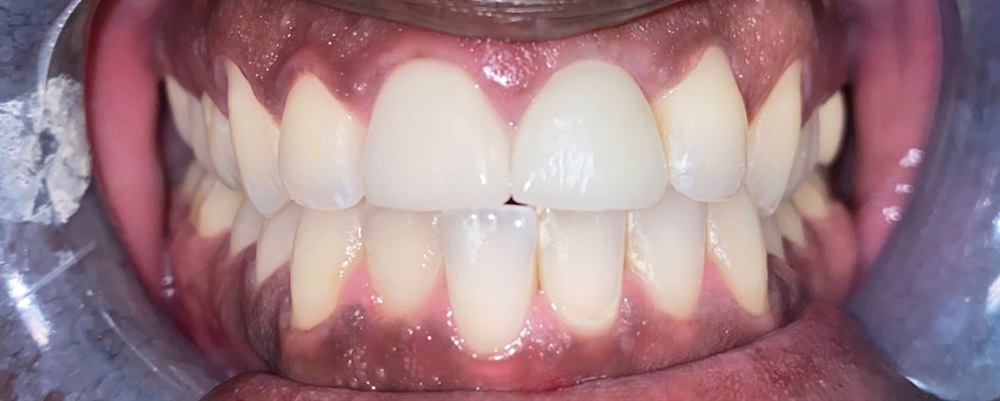

This remains one of my favorite cases because it really displays the success one can have with anterior implant cases. I was using a modified “dual zone therapy” technique (developed by Drs. D.P. Tarnow and S.J. Chu), which I have found to have great utility in an office where making immediate provisionals does not fit the workflow.

After